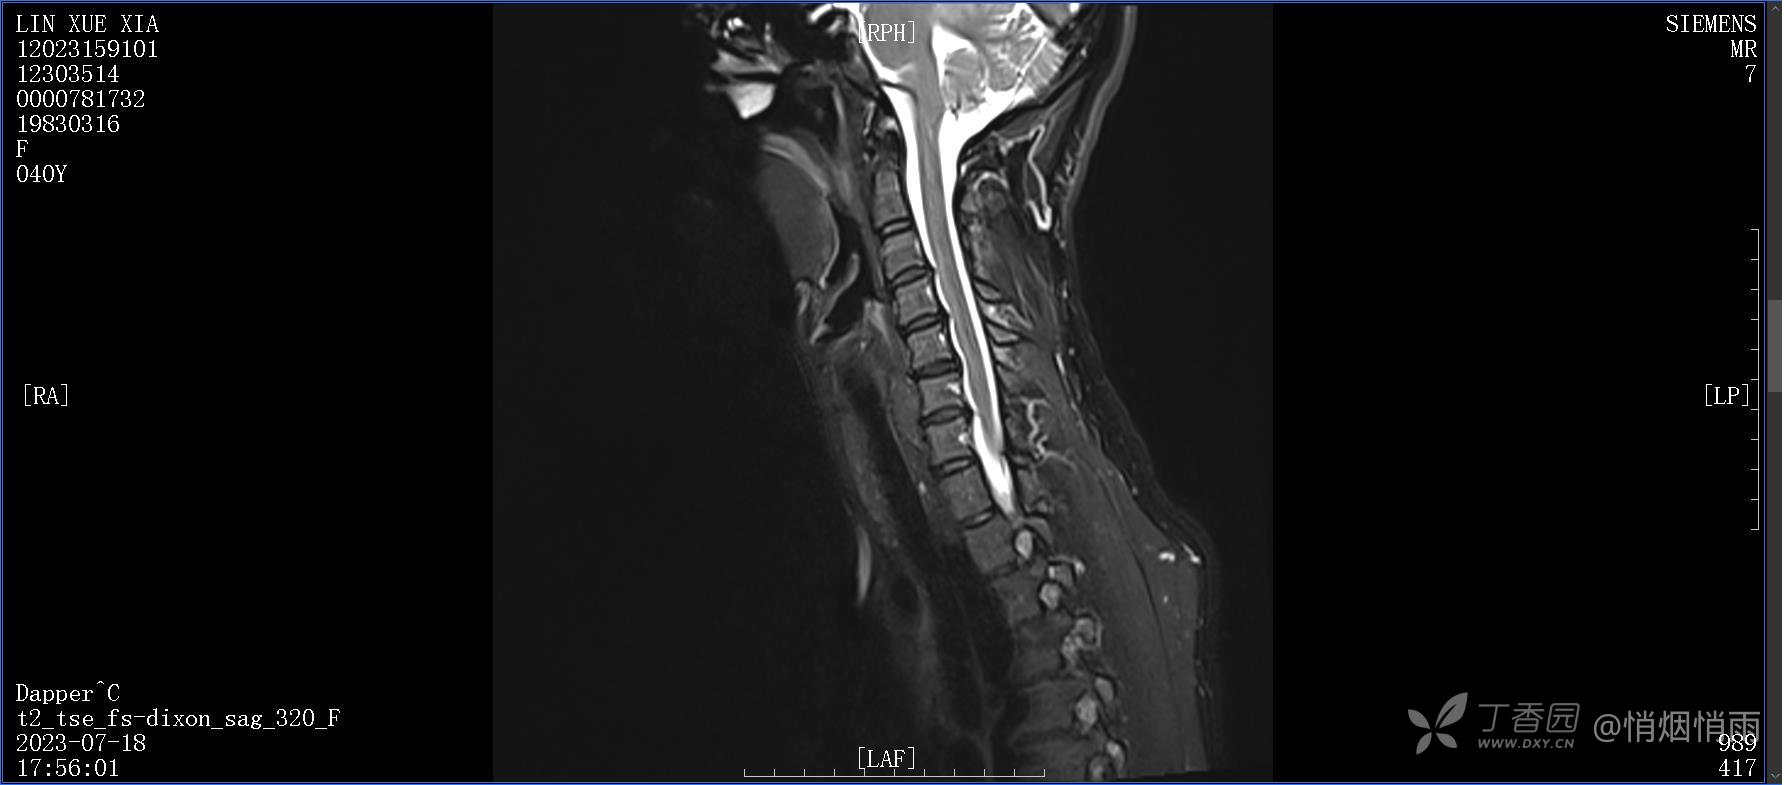

NeurothinkerZ 推荐患者女性,40岁,因右肩背部疼痛班活动受限4日余入院(2023-07-17)。

病史:入院前4天无明显诱因突然感右肩背疼痛伴随活动受限,自行口服依托考昔、艾瑞昔布等药物治疗,院外应用肩关节局部手法按摩等,均无明显改善。外院门诊诊为颈椎病。自诉既往多次“胸椎小关节紊乱”于当地诊所行手法按摩,治疗后好转,否认慢性疾病病史、外伤史、手术史,诉青霉素过敏,无其他药物食物过敏史,否认吸烟史、饮酒史,月经正常,经量正常。

目前的诊断,暂时依据辅助检查诊为肩袖损伤,但是患者疼痛的性质和特点,却不是单纯的肩袖损伤所致。考虑过胸廓出口综合征,但是该疾病会出现肩胛区的疼痛吗?(由于考虑到费用的问题,没再进行下一步的检查)带状疱疹会有如此的症状吗?